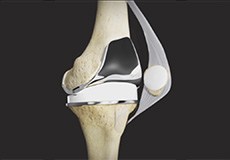

Tricompartmental Knee Replacement

Tricompartmental knee replacement, also called total knee arthroplasty, is a surgical procedure in which the worn-out or damaged surfaces of the knee joint are removed and replaced with artificial parts.